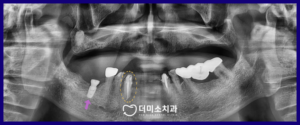

아래턱 오른쪽 어금니 부위에

임플란트 식립 후

충분한 시간이 지났을 때

최종 보철물 제작을 위한

인상채득을 진행하였으며,

아래턱 앞니와 마찬가지로

지르코니아 보철물로 마무리해 드렸습니다.

아래턱 치아의 치료가 마무리되어 갈 때쯤

위턱 전체 틀니 제작을 위한

위아래 교합 상태를 체크하고

치아 배열 후

최종 보험틀니 제작까지 마무리해 드렸습니다.